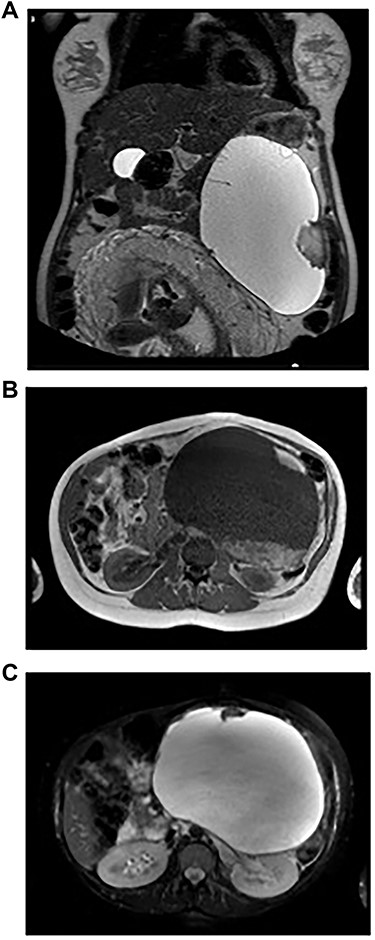

A 32-year-old woman at 31 weeks of pregnancy was referred to our hospital due to an abdominal mass detected during routine check-up. She had no notable medical history. The third-trimester routine abdominal ultrasound revealed the presence of a cystic lesion in the left upper abdomen, which was not noted in previous ultrasounds. Further evaluation with magnetic resonance imaging (MRI) revealed a complex cystic lesion (21 × 13 × 14 cm) arising in the left quadrant of the abdomen, involving the tail of the pancreas (Fig. 1a). The cyst had two solid components, the largest one with 5.2 cm (Fig. 1b). There were also a few septa inside the cystic mass (Fig. 1a and c). The diagnostic hypotheses were an idiopathic retroperitoneal hematoma, a pancreatic MCN or retroperitoneal cystic lesion. Despite its large volume, the patient did not present complaints and physical examination revealed normal.

Imaging studies. A: Abdominopelvic T2-weighted coronal MRI – Voluminous left supramesocolic cystic formation (24 cm × 17 cm × 13 cm), with well-defined contours and small septa and parietal vegetation inside. B: Abdominopelvic T1-weighted axial MRI – The lesion with a solid component hyperintense on T1-weighted imaging, translating eventual area of haemorrhage. C: Abdominopelvic T2-weighted axial MRI – The lesion pushed the stomach to the right and the spleen upward, as well as the kidney to the back, apparently without direct invasion of these structures.